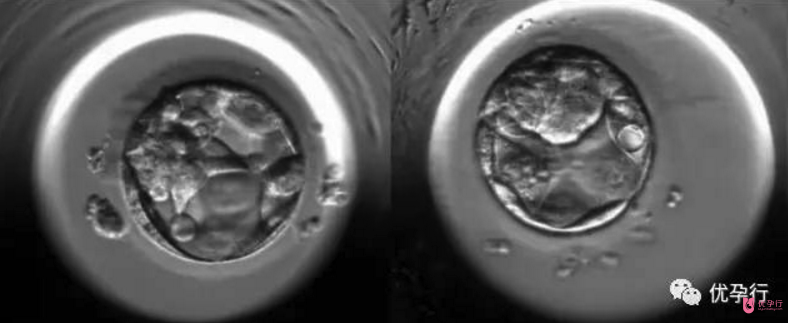

卵子和精子結(jié)合后形成受精卵,受精卵由輸卵管向子宮運(yùn)行中,不斷進(jìn)行細(xì)胞分裂,此過程稱卵,卵裂產(chǎn)生的細(xì)胞稱卵裂球。隨著卵裂球數(shù)目的增加,細(xì)胞逐漸變小,到第3天時(shí)形成一個(gè)12~16個(gè)卵裂球組成的實(shí)心胚,稱桑葚胚。在試管嬰兒操作中,會將這個(gè)在第3天形成的桑葚胚簡稱為早期胚胎,術(shù)前常說的鮮胚指的就是它。

桑葚胚的細(xì)胞繼續(xù)分裂,細(xì)胞間逐漸出現(xiàn)小的腔隙,大約2天后它們較后匯合成一個(gè)大腔,桑葚胚轉(zhuǎn)變?yōu)橹锌盏呐吲荨E吲菀簿褪悄遗?,這個(gè)時(shí)候是受精卵成活的第5天。早期胚胎發(fā)育到囊胚的這兩天是非常關(guān)鍵的,對溫度、空氣含氧量、二氧化碳含量的要求都非常高。